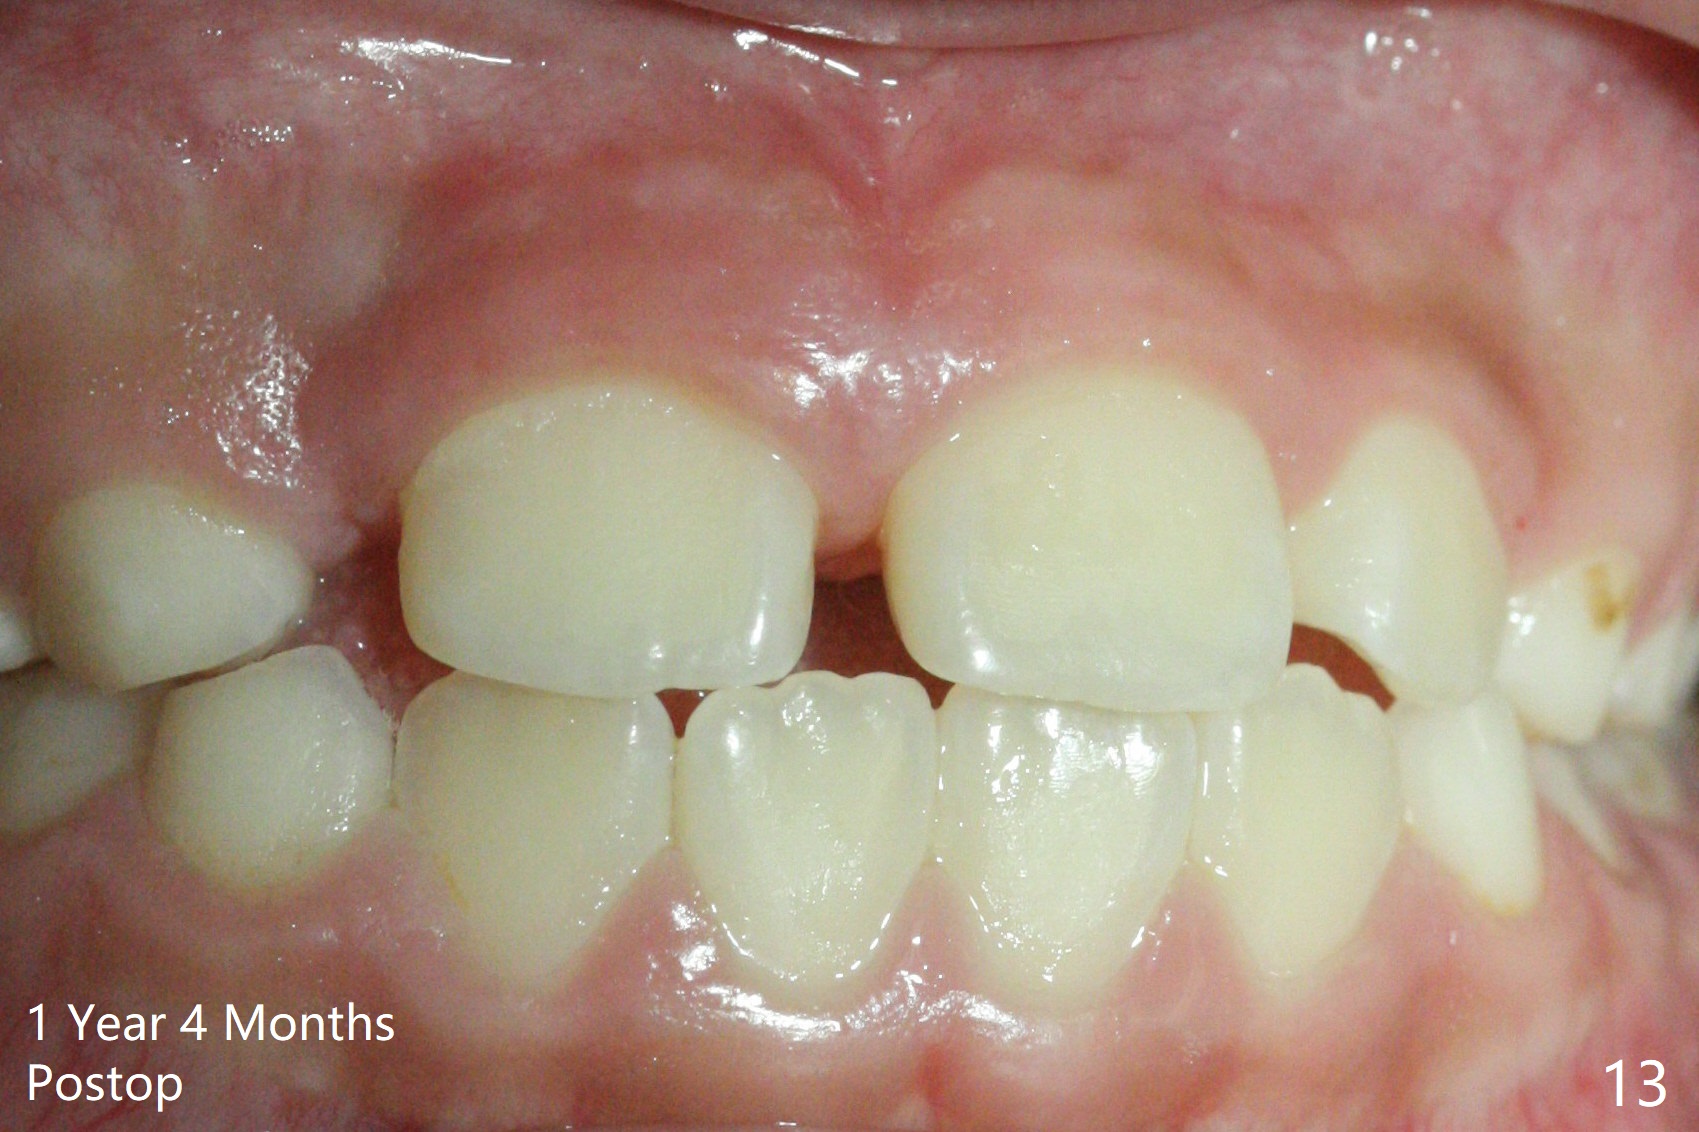

There is a large diastema between the upper central incisors (Fig.7). The left anterior palate is slightly elevated (Fig.8 *). In fact the cortex overlying the mesiodens (Fig. 9 *, 11 <) is to be removed with a surgical handpiece in order to extract the mesiodens (Fig.10). The left central shifts mesial in 7.5 months postop, whereas the right one remains in place (Fig.12). The tooth #7 is unerupted 1 year 4 months postop (Fig.13).